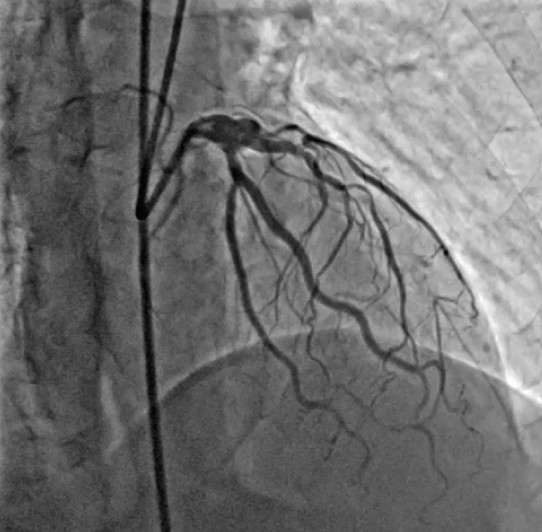

Chronic total occlusion of the mid LAD, with a blunt proximal cap. ¡¤ TIMI 0 flow distal to the occlusion. ¡¤ Distal LADvisualized via retrograde collateralfilling. ¡¤ Lesion length estimated to be >20 mm withmoderate calcification and tortuosity

Angiographyconfirmed a suitable anatomy for retrograde CTO PCI via septal-to-septalcollateral pathway using a single-catheter technique.Thepresence of navigable CC1–CC2 septal collaterals, clear visualization ofthe distal LAD,